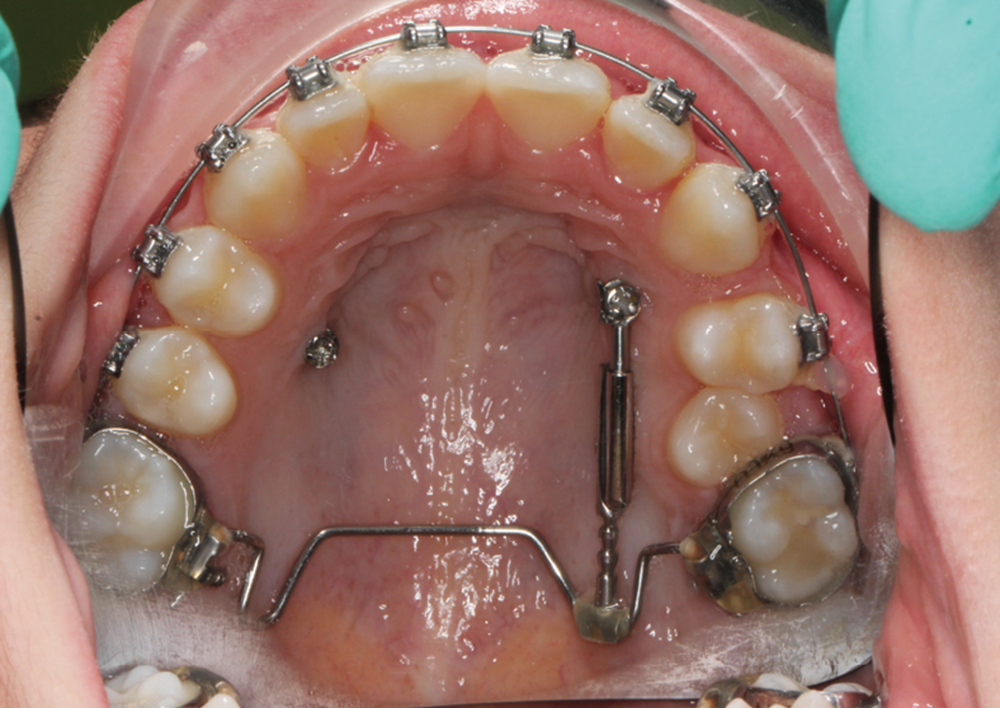

C’est à ces questions que nous permettront de répondre les deux premiers conférenciers, parodontologistes : le Dr Béatrice Straub nous présentera le renfort parodontal minéralisé, technique qu’elle a développée et pratique depuis de nombreuses années, pour éviter les préjudices des mouvements orthodontiques à risque, notamment lors des décompensations préchirurgicales (fig. 1a-d) ; le Pr Anton Sculean abordera le thème des greffes, avec leurs indications, les différentes techniques à privilégier et illustrera ses propos par de nombreux cas cliniques aux résultats esthétiques impressionnants.

À côté de la coopération moindre qu’ils exigent, les ancrages squelettiques présentent également l’avantage de répondre à des indications très variées : correction des sourires gingivaux (Dr Skander Ellouze, fig. 3a-c), distalisation ou mésialisation molaire, supports pour les masques faciaux, mini transpalatin sur vis après expansion, ressorts de rétraction pour mettre en place les canines incluses sans léser les racines des dents adjacentes [3] (Dr Stéphane Renger, fig. 4) ou appareils d’expansion maxillaire (Dr Hans Winsauer, Dr Guido Sampersmans, fig. 5a-c)…